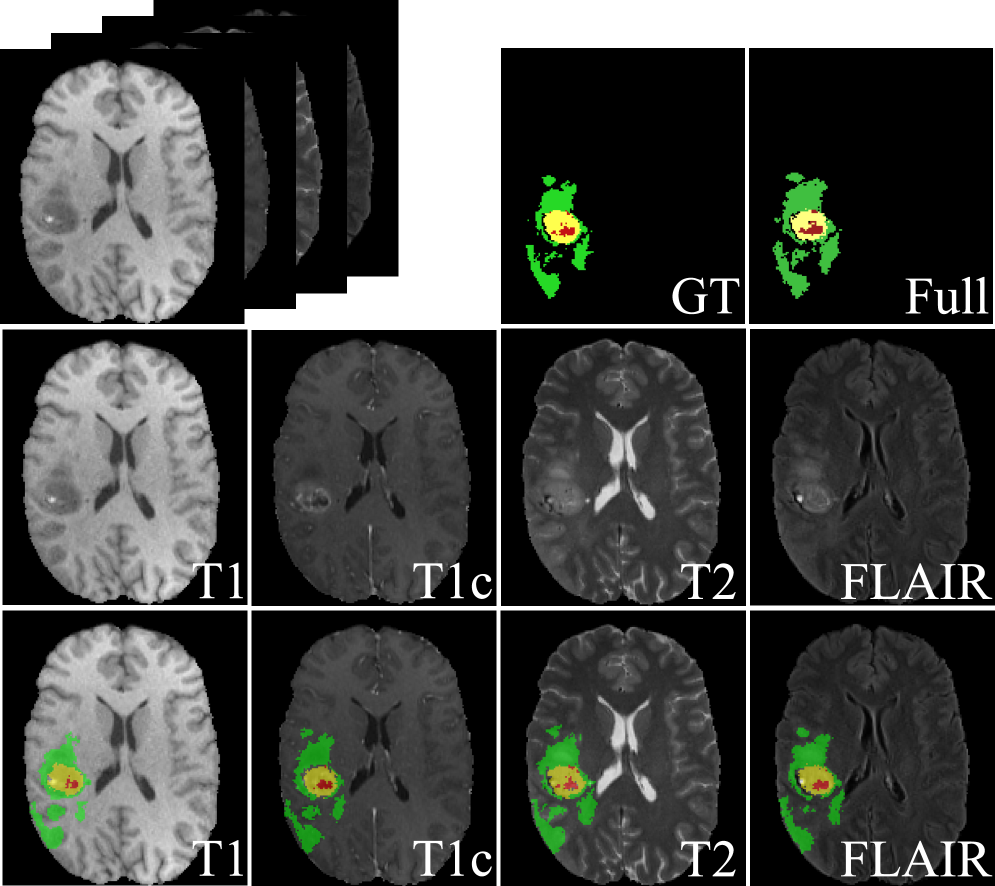

Refer to caption

Figure 3: Visualization. Green: edema; yellow: enhancing tumor; and red: necrotic and non-enhancing tumor core. GT: Ground Truth.

Table 1 showcases the performance comparison between our method and four recent state-of-the-art methods for missing modality brain tumor segmentation on the BraTS 2018 dataset. In terms of overall average performance, our method achieves the best results across all three segmentation regions: 62.70% for ET, 78.23% for TC, and 86.47% for WT, representing improvements of 1.93%, 0.3%, and 0.65% over the second-best method, respectively. Figure 3 shows example segmentation results by our method.

In single-modality scenarios, our method performs best in most cases, particularly achieving 90.40% for WT segmentation with Modality 1, significantly outperforming other methods. Our method also demonstrates stable advantages in other modality combination scenarios. More intuitive results are presented in Figure 4.